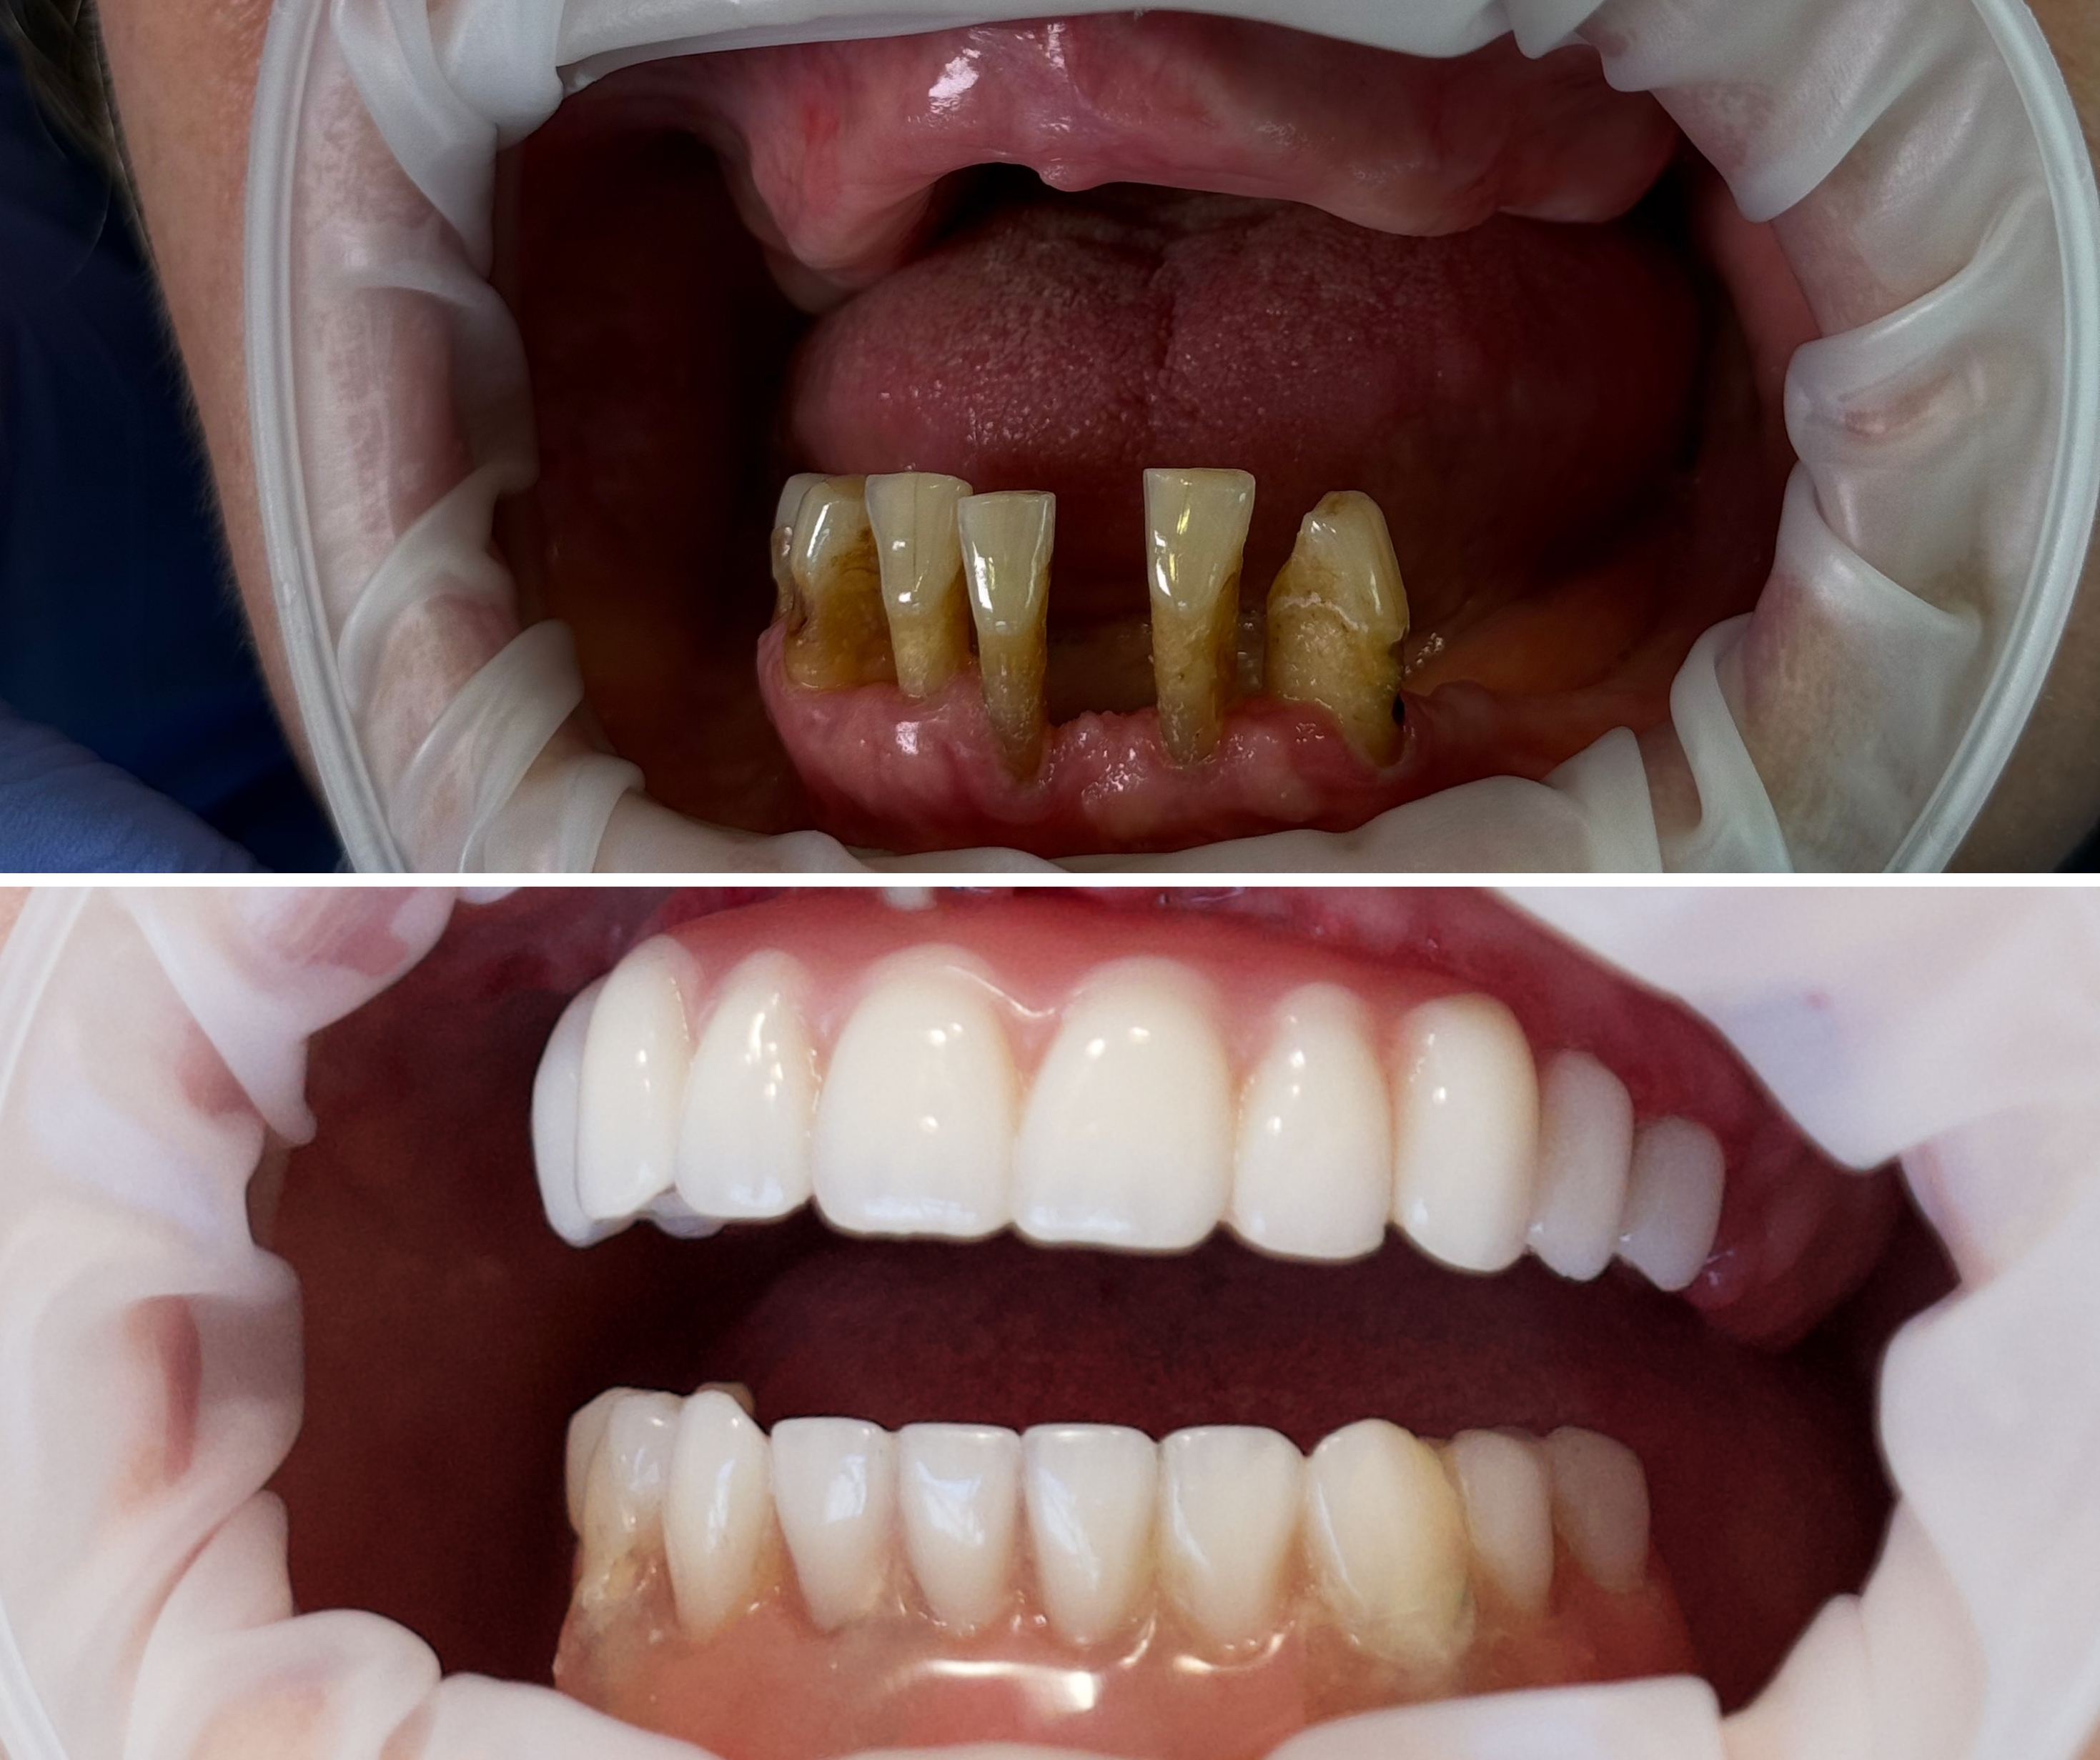

zespół specjalistów zakwalifikował Panią Jadwigę do zabiegu Malo Clinic Protocol – w stopniu Hybrid (połączenie implantów klasycznych i zygomatycznych) w szczęce oraz High Skill w żuchwie (cztery implanty klasyczne w miejscach o największej gęstości kości).

Dzięki nowoczesnej technologii i doświadczeniu zespołu udało się uniknąć przeszczepu kości, mimo znacznego zaniku.

Zabieg – nowe zęby w 1 dzień

W dniu zabiegu przeprowadzono:

- Usunięcie zębów, które nie nadawały się do zachowania,

- Wszczepienie czterech implantów w górnym łuku (2 klasyczne z przodu i 2 zygomatyczne w kości jarzmowej),

- Wszczepienie czterech implantów klasycznych w żuchwie,

- Osadzenie dwóch mostów tymczasowych Malo Clinic Bridge, wykonanych tego samego dnia w laboratorium protetycznym.

- Już po kilku godzinach Pani Jadwiga mogła jeść, mówić i uśmiechać się bez obaw.

Efekty leczenia – nowy rozdział życia

Efekty:

- Stabilny, naturalny uśmiech – bez wypadania protez,

- Odmłodzony wygląd i większa pewność siebie,

- Możliwość jedzenia bez ograniczeń,